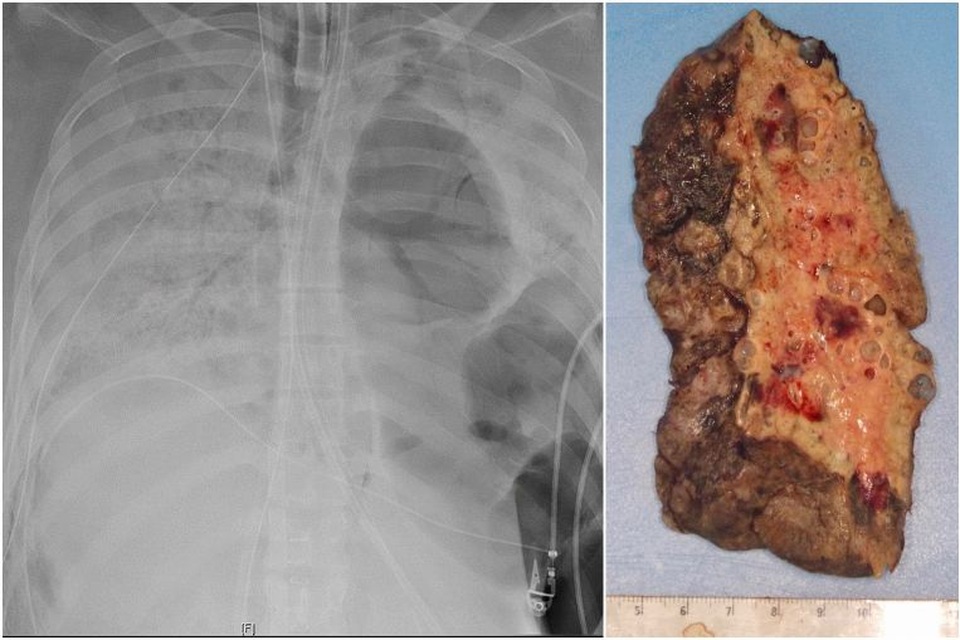

Phổi đông đặc của bệnh nhân mắc Covid-19 trước khi được cấy ghép tại Mỹ

Phổi của bệnh nhân bị tổn thương nghiêm trọng trước khi được ghép tại Chicago. (Ảnh: AFP)

Tới đầu tháng 6, hai lá phổi của bệnh nhân này bị tổn thương nghiêm trọng tới mức các bác sĩ quyết định rằng, ghép phổi là phương án duy nhất để giữ mạng sống.